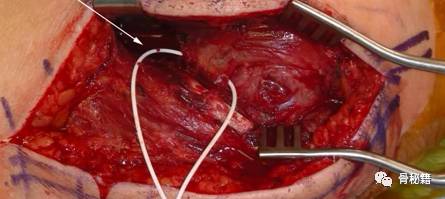

该腋神经横跨肱骨干,需要小心分离保护,不能过度牵拉

然后就可以进入肱骨近端了,整体暴露图 上方为小结节,下方为大结节。

1、用4843缝线,分别将肩袖、大结节、小结节处进行缝合